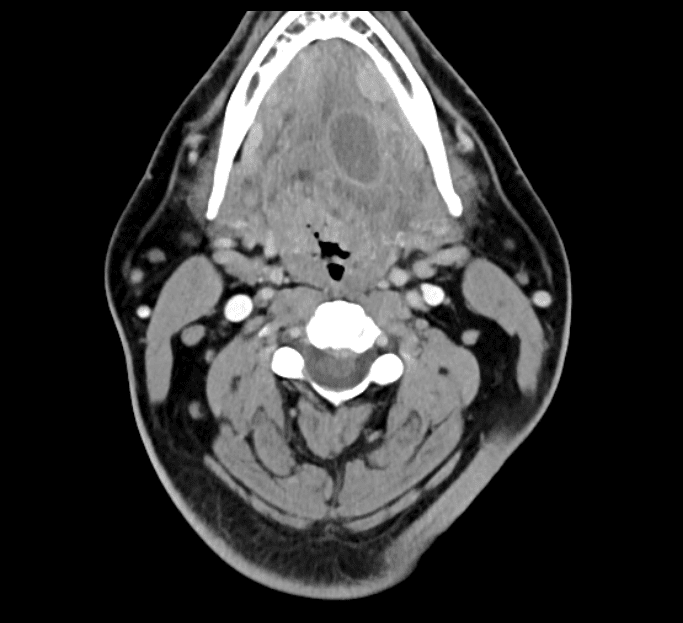

The MRIOnline Imaging Mastery Series: Pathology of the Oral Cavity and Oropharynx 2020 (CME VIDEOS) provides a comprehensive on-demand review of imaging related to the oral cavity and oropharynx. Presented by Dr. Suresh Mukherji, this course employs a practical approach to understanding the anatomy and a range of pathologies, including neoplasms, infections, and congenital and vascular malformations in these complex regions.

This course delivers detailed imaging education on a wide spectrum of oral cavity and oropharyngeal pathologies, reinforcing proficiency in case assessment and diagnostic interpretation.

• Left Glossotonsillar Sulcus SCCA CT

• Right Glossotonsillar Sulcus Ca Classic

• Floor of Mouth SCCA Carcinoma

• Left Tonsilar Cancer

• Alveolar Ridge CA

• Mandibular Lymphoma

• ACC of the Oral Cavity

• SCC of the Tonsil

• Tonsilar Cancer – Why it’s Not a Glomus Tumor

• Right Tongue Base SCCA

• Tonsilar Phlegmon

• Ludwig’s Angina

• Oral Abscess

• Suppurative Adenitis with Retropharyngeal Effusion

• Pharyngeal Trauma

• Bilateral Ranulas

• Venolymphatic Malformation of Right Face/Oral Cavity

• Lymphatic Malformation

• Mixed Vascular Malformation

• Oropharynx Anatomy